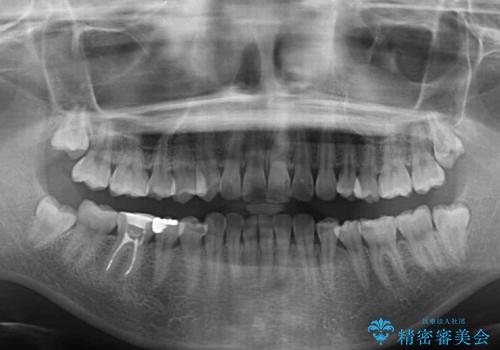

- 上下前歯の突出感とデコボコを気にして来院された患者様です。

インビザラインによる上下歯列の側方拡大と後方移動、IPR(歯と歯の間を削る)にるスペースの獲得により歯列を整えることとしました。

骨格的な左右差があったため、上下の正中を合わせることができませんでした。

骨格の差は改善できないため、奥歯の咬み合わせに物足りなさを感じましたが、奥歯の咬み合わせによる不自由はなく、口元の突出感も改善することができました。